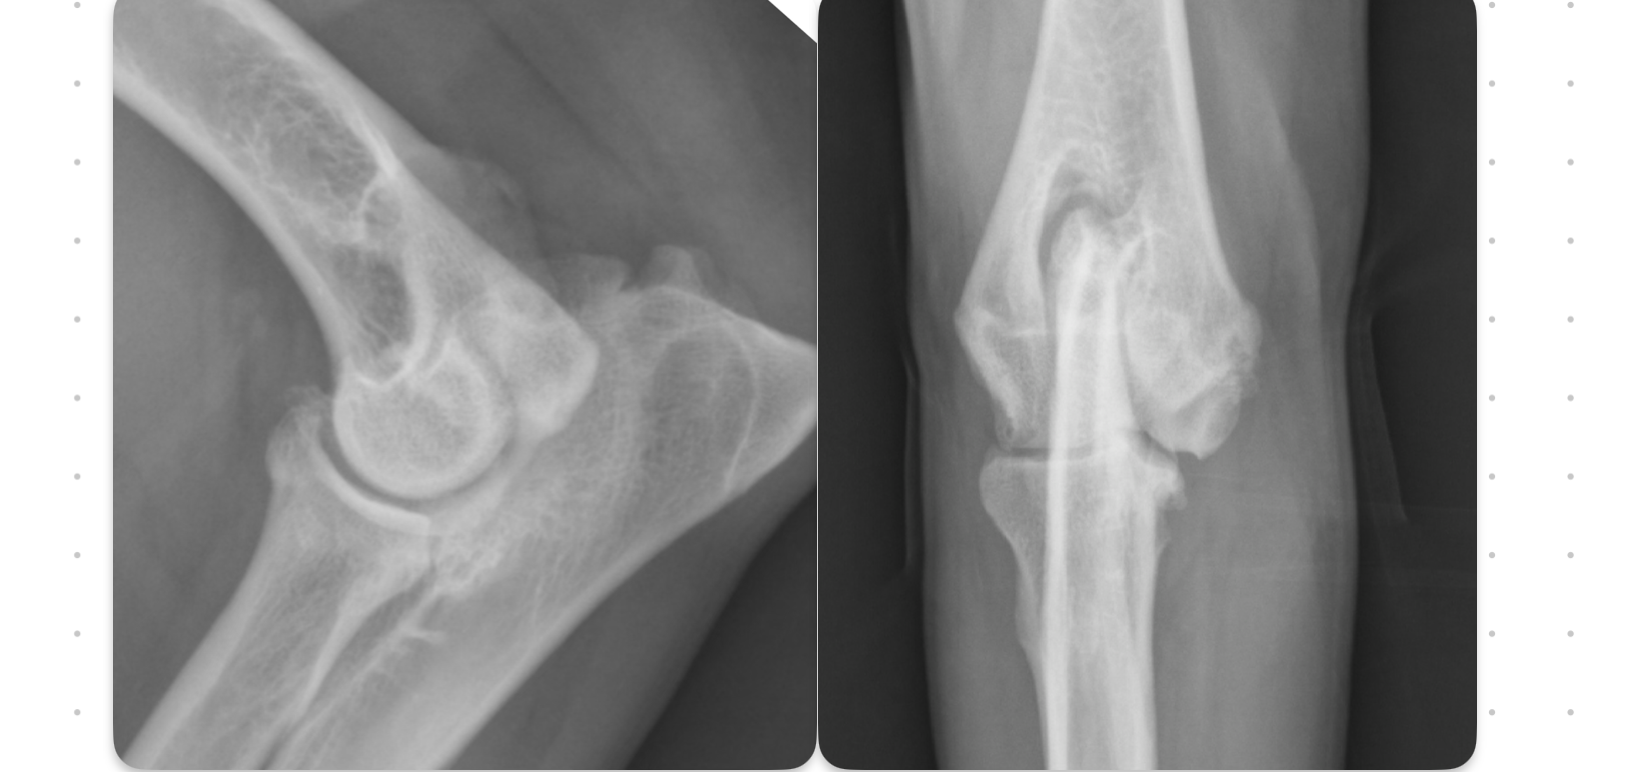

which OCD lesions are these in the dog

A = cd humerus

B = medial humeral condyle (elbow)

C = medial trochlear ridge (ankle)

D =lateral femoral condyle (knee)